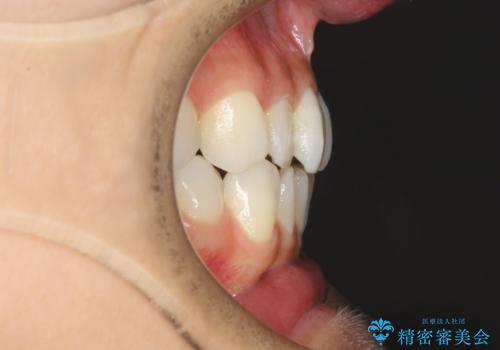

軽度の前歯のガタガタをインビザラインでの目立たない矯正

- 前歯のガタガタを主訴に来院されました。

軽度であったため、枚数制限のあるタイプのインビザラインのプランで治療することとしました。